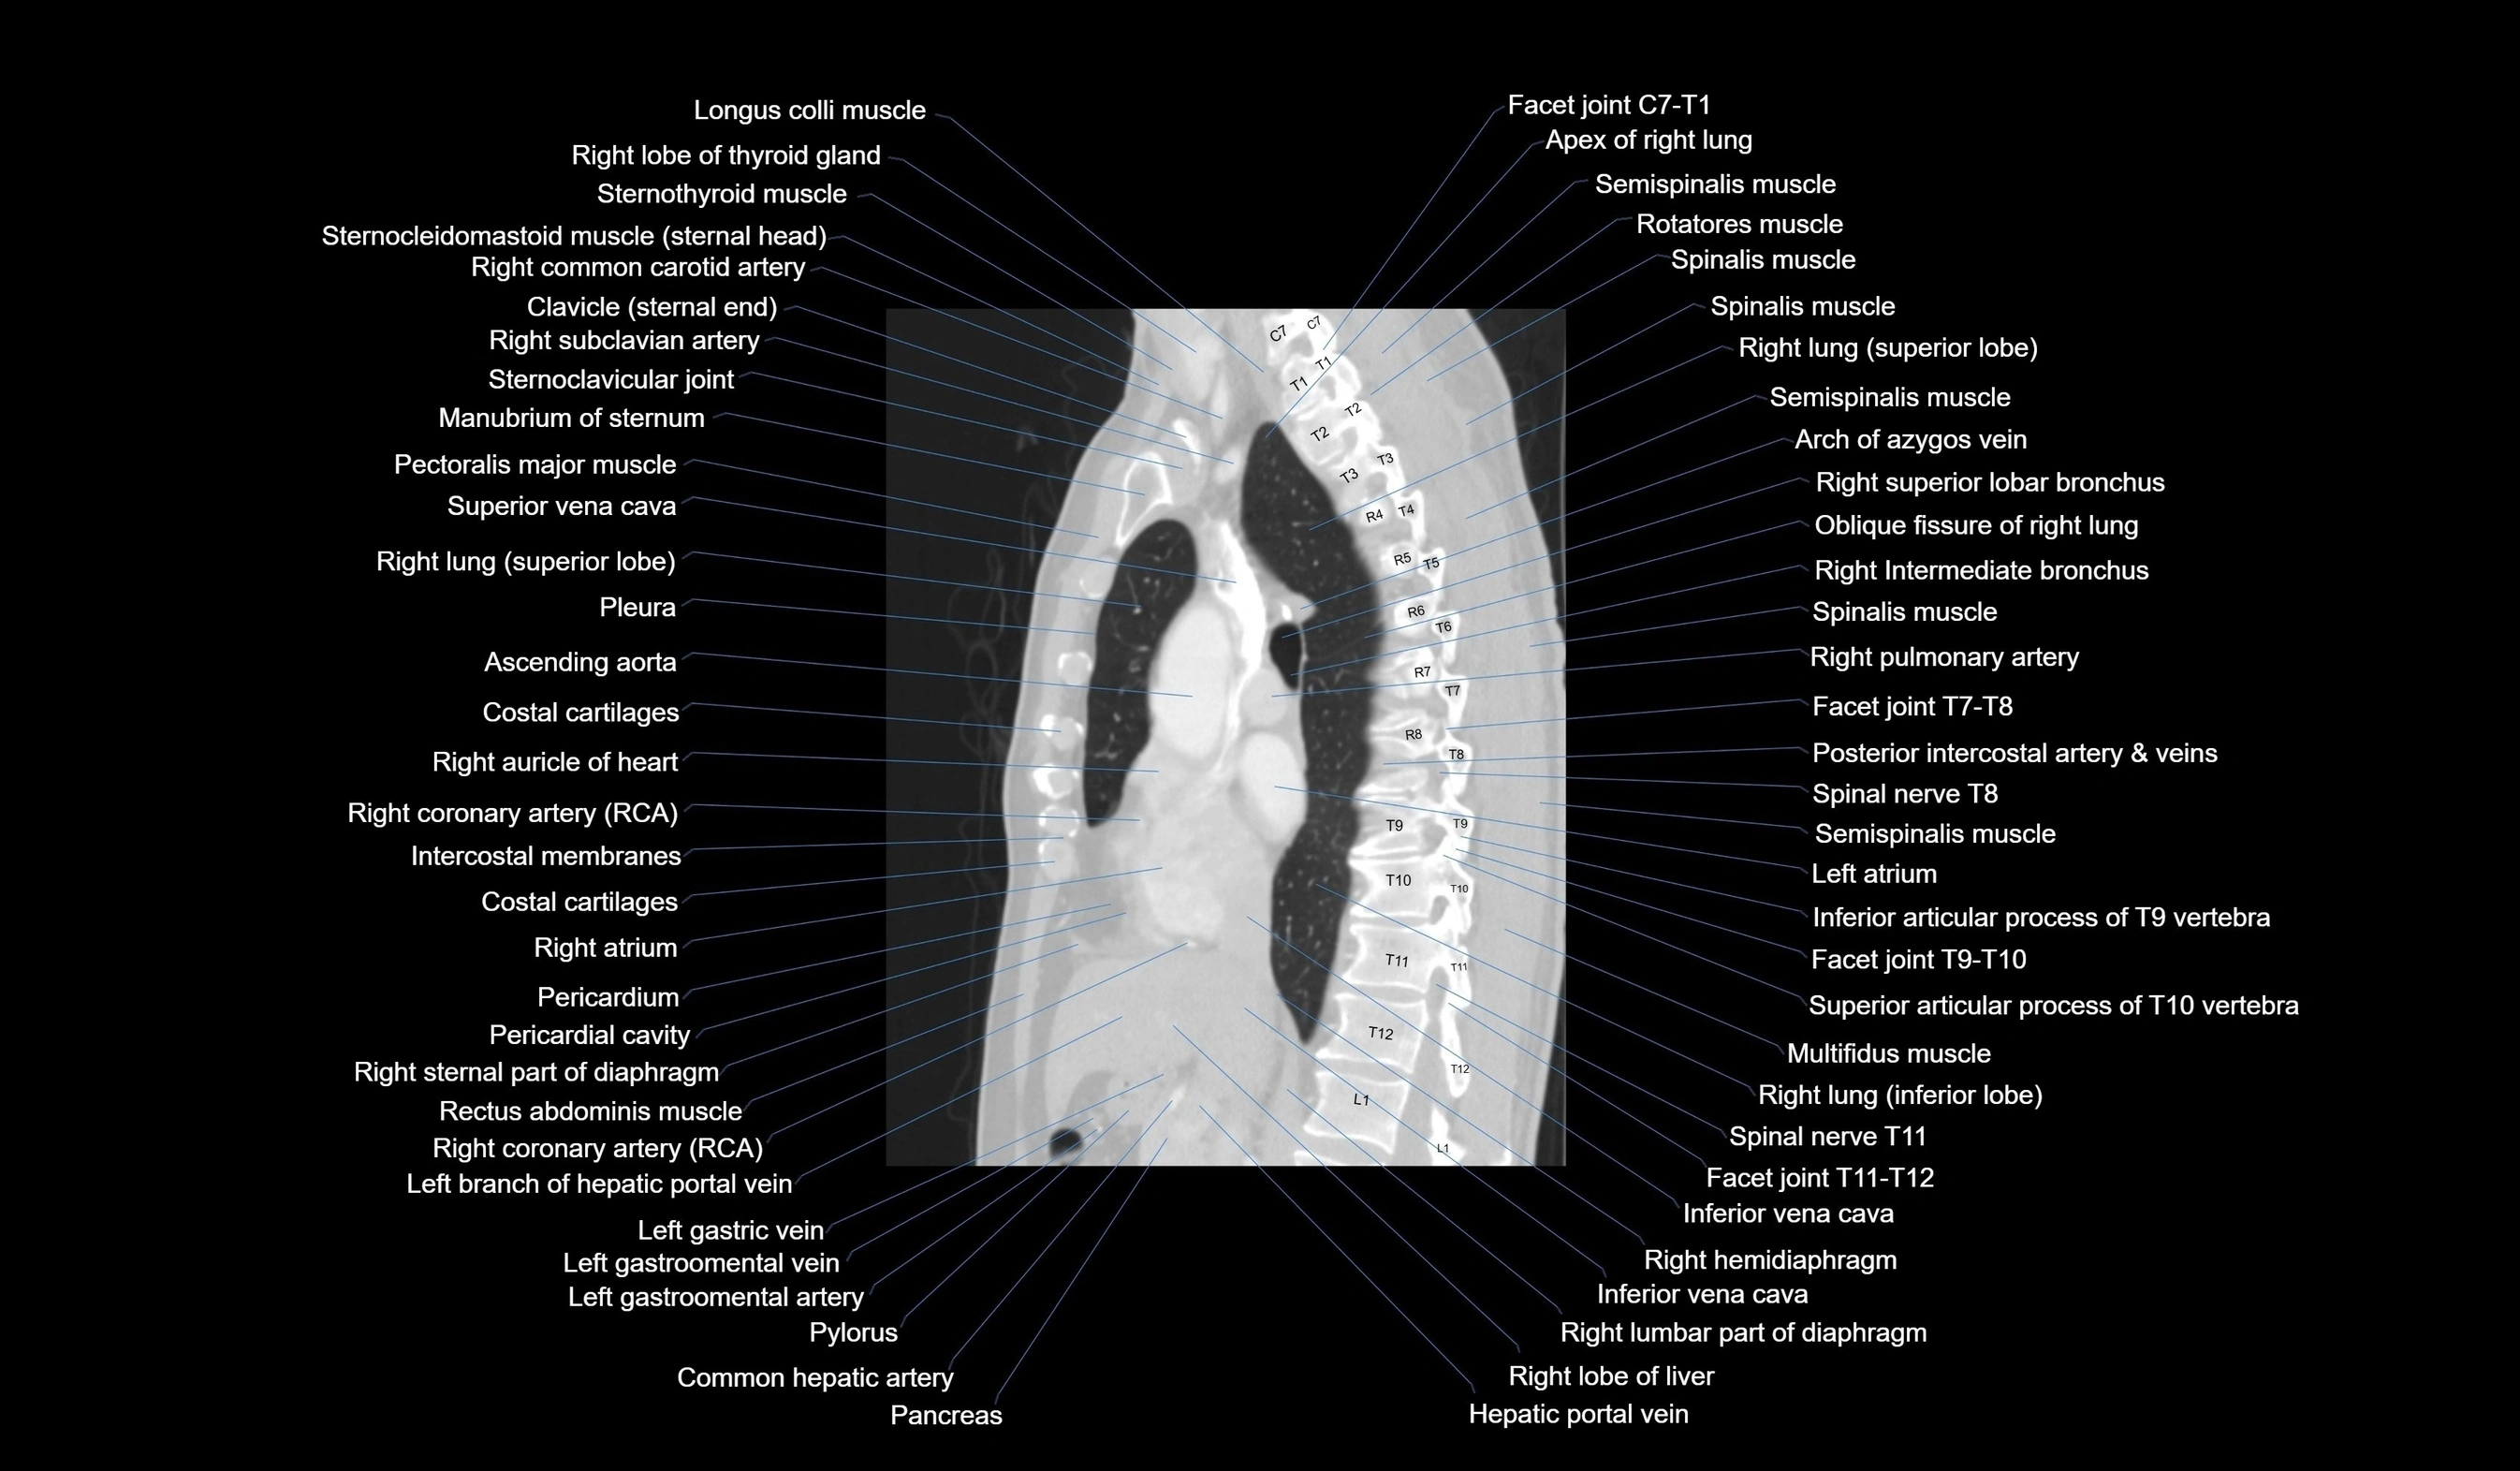

CT images